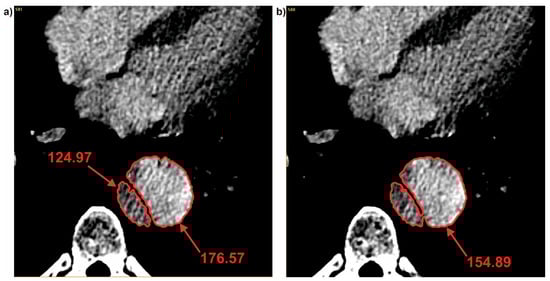

3.2. Brightness Value Analysis

| Patient | Average Brightness | ||

|---|---|---|---|

| Common | True | False | |

| Pat I | 184.73 ± 16.75 | 141.36 ± 20.26 | 178.01 ± 6.04 |

| Pat II | 331.11 ± 18.41 | 364.03 ± 14.10 | 320.10 ± 12.60 |

| Pat III | 291.13 ± 6.60 | 213.52 ± 39.70 | 313.91 ± 8.62 |